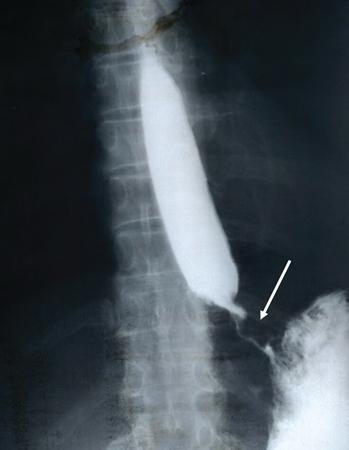

Carcinoma distal oesophagus

Barium oesophagogram in a 50-year-old male patient showing asymmetric mural thickening, ‘shouldering’, mucosal irregularity with a long segment of luminal narrowing (arrow). There is upstream hold-up of contrast and dilatation of the oesophagus.

In case of gastric carcinoma with extension into GE junction, associated fundic mural thickening and mucosal irregularity may be seen.

Image

Fig. 7.4.3.3 Barium oesophagogram showing carcinoma distal oesophagus.